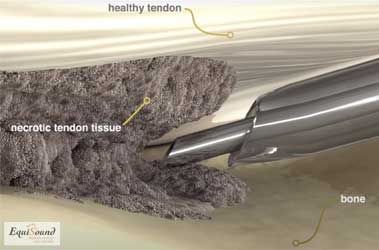

Procédure Tenex chez un cheval debout : à l’aide d’un débridement tissulaire par ultrasons sous échoguidage, on procède à l’élimination du tissu dégénératif chez ce cheval présentant une lésion dégénérative chronique du suspenseur du boulet.

Tenex est une technique de traitement développée il y a 5 ans aux États-Unis pour traiter des pathologies tendineuses chroniques chez l’être humain (atteinte chronique des tendons d’Achille, épine calcanéenne, dégénérescence du tendon rotulien, etc.). Cette technique utilise des ultrasons (comme pour un détartrage) afin de détruire le tissu endommagé et de stimuler ainsi le processus de cicatrisation pour offrir une nouvelle chance de guérison. La fréquence ultrasonore est spécifiquement choisie pour ne détruire que les tissus durs (fibrose et minéralisations) et ne pas causer de dommages au tissu tendineux sain. Le traitement par ultrasons est appliqué à l’aide d’une aiguille creuse dans un tube creux (cf. photo 8a). Durant le traitement, un flux de NaCl sort de l’aiguille creuse et est simultanément aspiré via le tube creux (cf. photos 8b et 8c). Cette solution aqueuse permet avant tout l’évacuation du tissu débridé mais aussi le refroidissement de l’aiguille qui chauffe fortement en raison des ultrasons.

L’aiguille étant introduite de manière échoguidée via des incisions de ponction dans la peau, ce traitement est mini-invasif. De ce fait, le patient récupère plus rapidement et nécessite peu de soins de plaie. Ceci permet aussi le positionnement exact de l’aiguille dans la zone dégénérative de la structure pathologique.